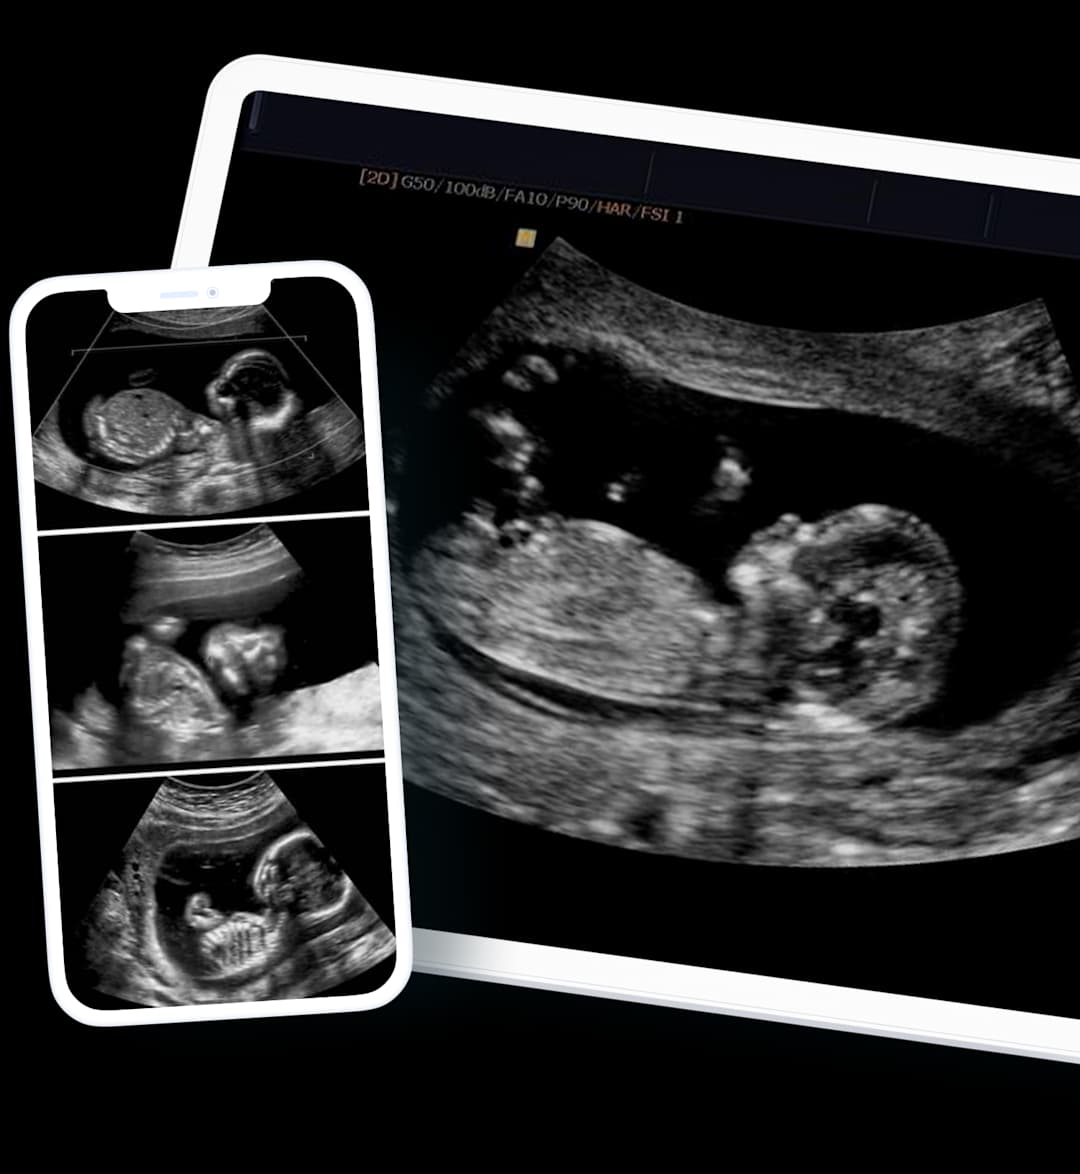

In addition to the report, images of your scan will be sent for you to share with a healthcare specialist of your choice.

Images from the scanner are projected on a screen, and, from here, the specialist can measure the size of your AAA.

We can provide scan images directly to your smartphone, often on the same day following your appointment. Gain the peace of mind and insight you need, without delay.